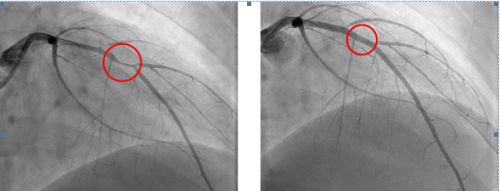

放置架前,血管严重狭窄(左);放入冠脉支架后,血管狭窄得到解决(右)。

18岁,人生才刚刚开始就要带上心脏支架生活?心内科主任郑昭芬组织团队会诊后,建议小浩植入可吸收心脏支架,这种生物支架几年后就能降解。在征得小浩本人和家人同意后,心内三科主任潘宏伟等利用血管内超声引导,顺利为他植入一枚生物可吸收心脏支架,拆除了其体内的“炸弹”。